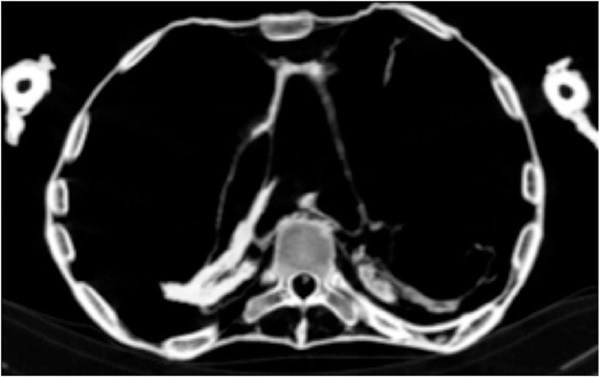

Các nhà khoa học đã sử dụng công nghệ cắt lớp máy tính để tìm hiểu và kết luận rằng "công chúa gào thét" qua đời bởi một cơn đau tim nghiêm trọng - đây cũng là nguyên nhân khiến xác ướp này chết trong tư thế mở miệng.

Nghiên cứu được thực hiện bởi nhà Ai Cập học Zahi Hawass và Sahar Saleem, giáo sư X quang tại Đại học Cairo - nhóm nghiên cứu đã phát hiện ra rằng căn bệnh xơ vữa nghiêm trọng của động mạch vành đã dẫn đến cái chết đột ngột.

Họ tin rằng khi công chúa qua đời, xác của cô vẫn chưa được phát hiện cho tới nhiều giờ sau. Đây là nguyên nhân khiến các khớp xương trở nên cứng và khó dịch chuyển, khiến từng phần của các cơ co lại. Kết quả chụp cắt lớp cũng cho thấy cô bị xơ vữa động mạch vành phải, động mạch vành trái, động mạch chủ bụng, động mạch chậu và các chi dưới.